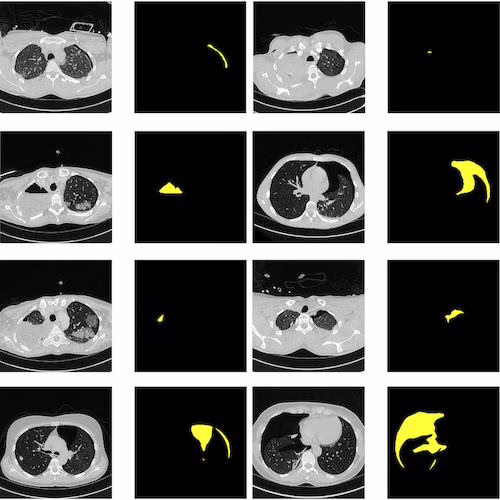

Deep Learning Detection and Quantification of Pneumothorax in Heterogeneous Routine Chest Computed Tomography

We are honored that Thomas Schlegl’s (our Machine Learning expert’s) recent article “Deep learning detection and quantification of pneumothorax in heterogeneous routine chest computed tomography” – a joint work of Medical University of Vienna and contextflow – was chosen to be featured in the April edition of the newsletter Highlights from the ESR Journals! Congrats to the entire team!